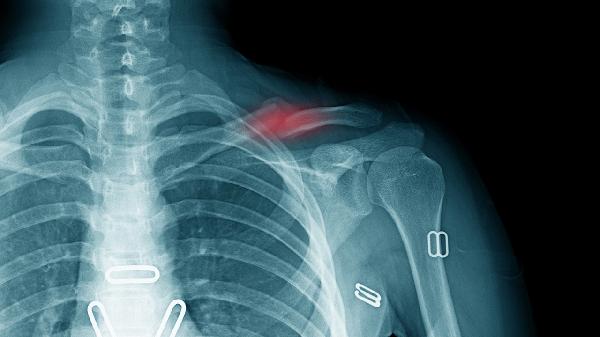

车祸撞击或运动损伤可能导致锁骨骨折后畸形愈合,形成骨痂压迫神经血管。此类患者多有明确外伤史,症状在受伤后数月逐渐显现。康复治疗包括物理疗法改善姿势,严重者需行锁骨复位内固定术。伴随症状可见患侧上肢皮肤温度降低。